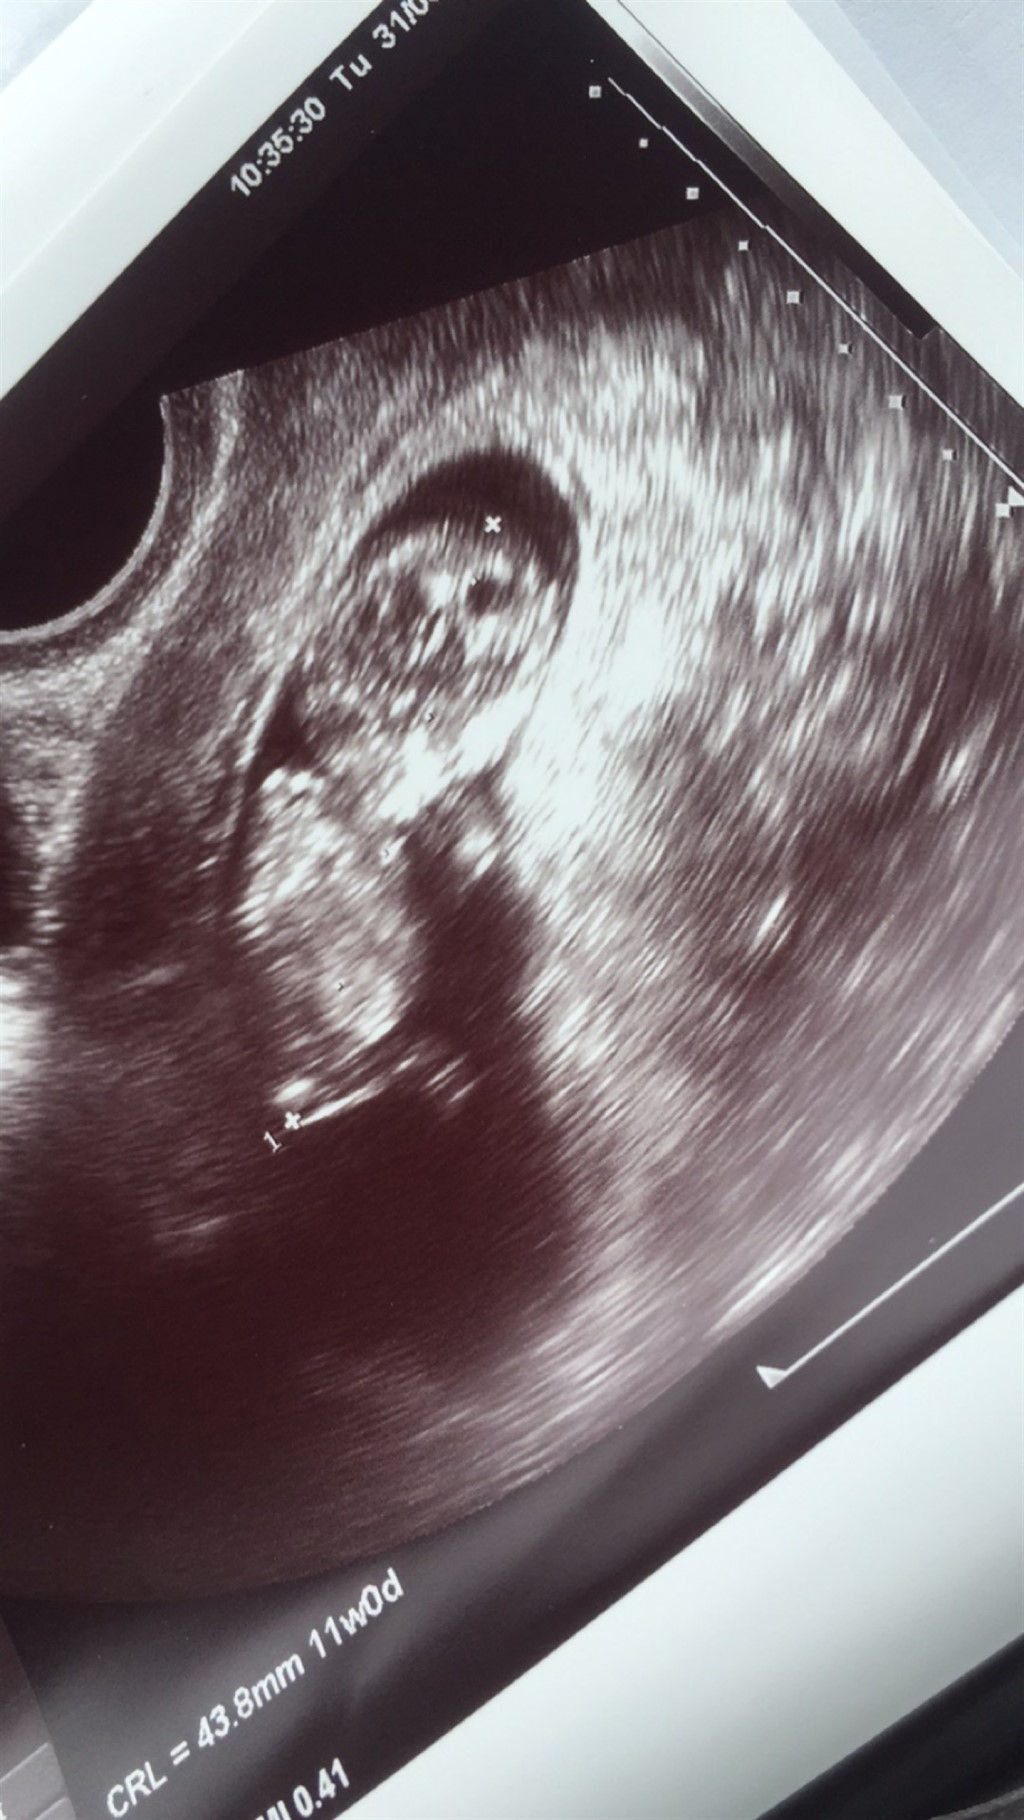

Blev scannet igår , bare sådan en ekstra hygge scanning . En dejlig livlig baby der hoppede og sparkede rundt .

Er 11 + 1 idag . Kan i måske se om det er en dreng eller pige

ved godt det er tidligt men bare for sjov hihi